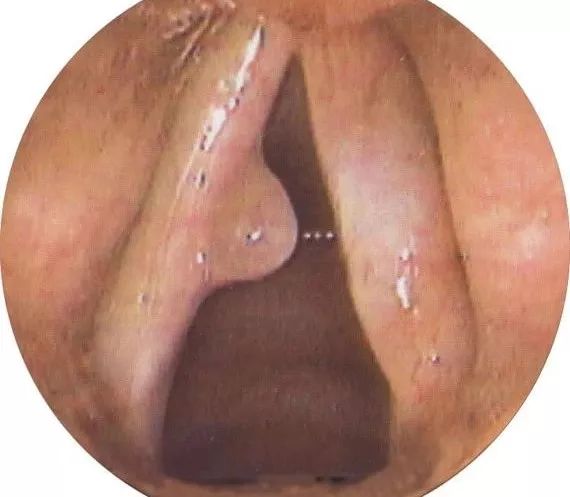

声带息肉在临床上比较常见,病因尚不十分清楚,可能与长期发声不当、长期不良刺激或慢性炎症有关。主要表现为声嘶,嘶哑程度因息肉大小和部位不同而异,轻者仅有轻微声音改变,重者嘶哑明显甚至发声困难。

声带息肉不仅可影响正常生活和工作,若息肉较大阻塞喉腔,可引起呼吸困难。

声带息肉的致命*伤杀**力在于突发癌变。

但很多息肉在癌变后,患者并没有很强的不适感,息肉就不知不觉发展,不知不觉癌变。

因此,一旦出现声音嘶哑、喉部异物感、咽喉干痒疼痛,建议立即到医院做纤维喉镜明确诊断,必要时也可在医生建议下做手术摘除。